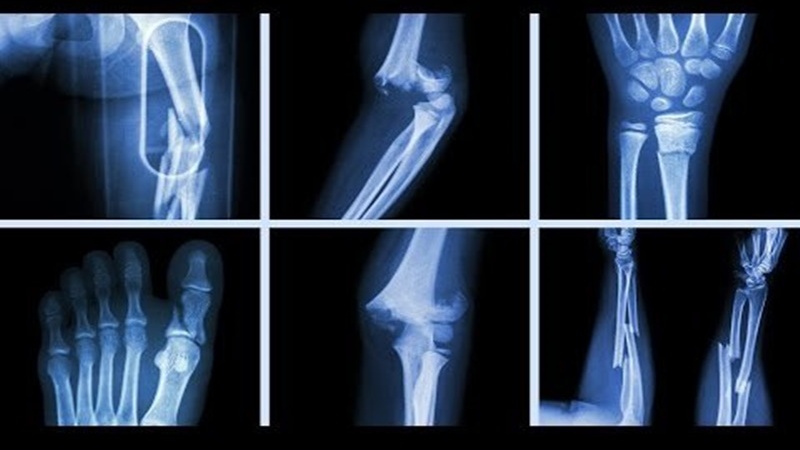

Bạn đã từng không may bị gãy xương do tai nạn hay do một sự cố nào đó chưa? Nếu có, vậy thì bác sĩ đã dùng những loại nẹp cố định nào để tiến hành chữa trị cho bạn? Hãy cùng Nhà thuốc Long Châu tìm hiểu các loại nẹp cố định gãy xương thông qua bài viết dưới đây bạn nhé.

Nẹp cố định gãy xương là gì và các loại nẹp cố định gãy xương phổ biến bạn cần biết sẽ được bật mí thông qua bài viết dưới đây. Dù chưa từng gãy xương hay bạn đã không may gặp phải trường hợp này, bạn cũng nên tìm hiểu về các loại nẹp cố định để hiểu rõ hơn mục đích và công dụng của chúng trong việc cố định gãy xương nhé.